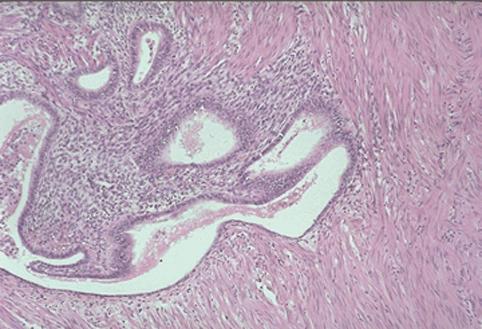

疾患(病理主体)の分類腫瘍様病変/子宮内膜症

部位(臓器別)大腸/S状

検査方法ミクロ

病変の最大径(ミリ)40以上